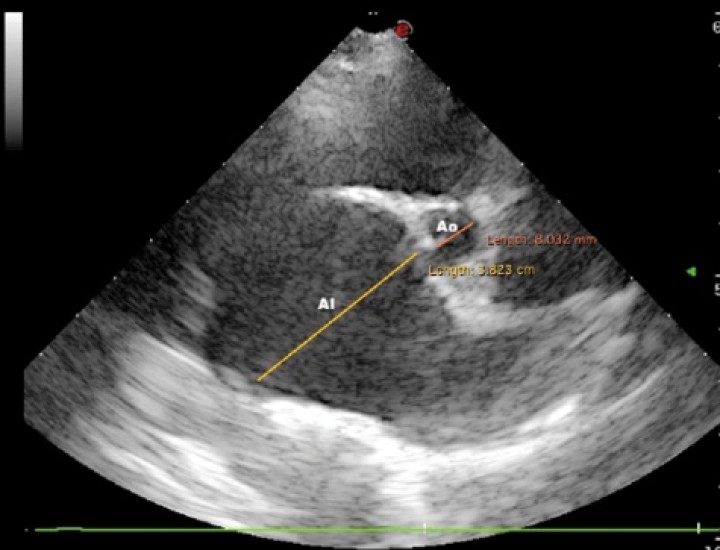

<p>Imagen ecocardiográfica paraesternal derecha en eje corto a la altura de la base cardiaca en la que se observa un aumento del ratio atrio izquierdo/aorta (AI/Ao= 4,76; normal <1,6). AI: atrio izquierdo; Ao: Aorta.</p>

Figura 3

Imagen ecocardiográfica paraesternal derecha en eje corto a la altura de la base cardiaca en la que se observa un aumento del ratio atrio izquierdo/aorta (AI/Ao= 4,76; normal <1,6). AI: atrio izquierdo; Ao: Aorta.

Se trata de la enfermedad cardiaca más frecuente en el paciente canino, suponiendo aproximadamente un 75 % de las cardiopatías.[ Keene BW, Atkins CE, Bonagura JD, et al: ACVIM consensus guidelines for the diagnosis and treatment of myxomatous mitral valve disease in dogs. J Vet Intern Med 2019; 33: 1127-1140. [pubMed] ] Podemos hablar de ella como una enfermedad idiopática, hereditaria y degenerativa de la válvula atrioventricular izquierda que podría llevar a generar insuficiencia valvular (Figs. 2 y 3).

Atendiendo a su fisiopatología, el cierre incompleto de la válvula resulta en una regurgitación del ventrículo izquierdo (VI) hacia el atrio izquierdo (AI) durante la sístole. Este flujo turbulento genera el soplo cardiaco. Esta regurgitación terminará causando congestión de la circulación pulmonar, edema de pulmón e hipertensión pulmonar. No olvidemos también que esta alteración podría conllevar una reducción significativa del GC y la activación de los mecanismos compensatorios maladaptativos.